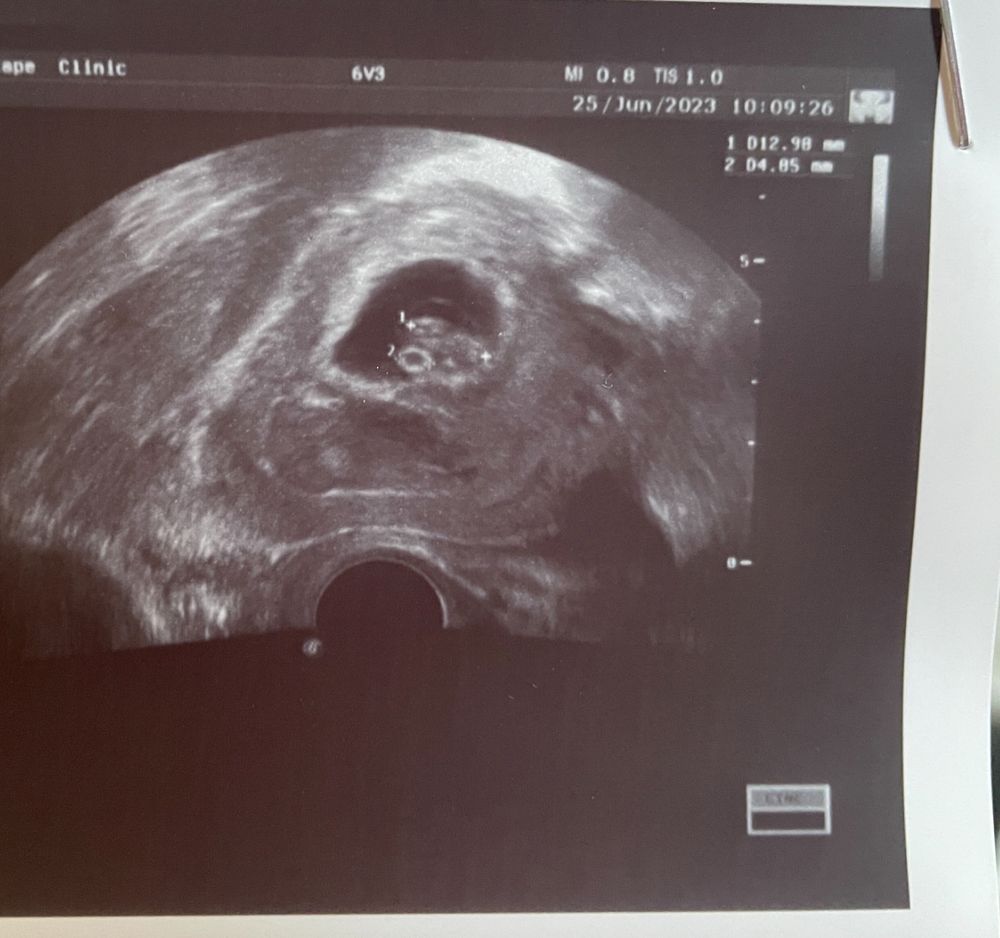

Вот ровно 35 дпп с сыном, я даже не знала, что это мало! 13 мм ктр! Все у вас отлично! Изображение

Best mammy , ну 13 это уже хорошо. Лучше чем 12

Анюта, там чуть не в ту точку поставить датчик, и вот уже плюс минус 1 мм